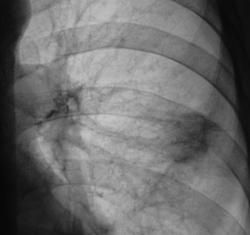

Сегодня, после проведения противовоспалительной (неспецифической) терапии пациент дан на контроль.

Прямая проекция.

Такое ощущение, что тень стала меньше? Может аутоиммуной природы процесс?

но ведь патология есть! тень была больше, стала чуть меньше! динамика есть! осталось определить, что это?